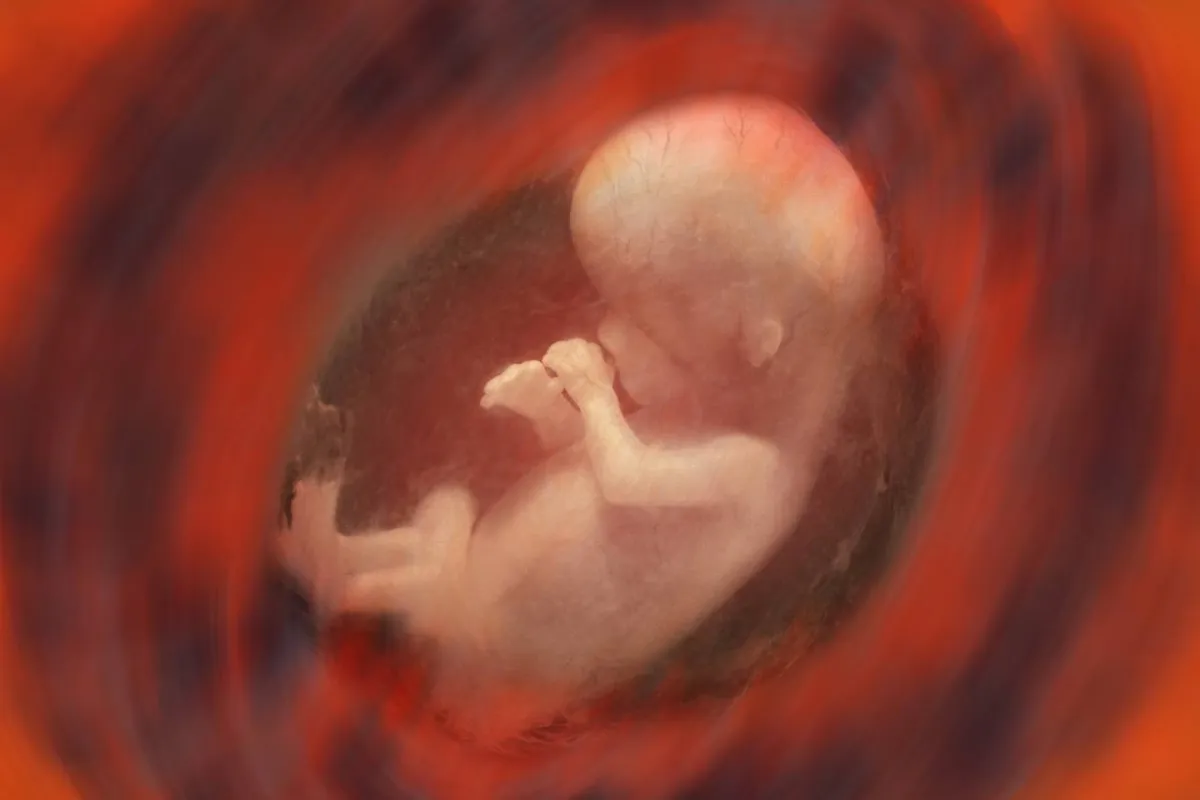

4. تظهر علامات الذكورة والأنوثة

حتى قبل الولادة ، يبدأ الجهاز التناسلي الصغير للطفل في الاستعداد. بين الأسبوعين 20 و23، يبدأ الصبي بالفعل في إنتاج الحيوانات المنوية. في ذلك الوقت، يكون مبيض الفتاة ورحمها مكتملا التكوين بشكل كامل، مع تزويدها بالبويضات مدى الحياة.

9. الطفل يستطيع رؤية الضوء

في حوالي الأسبوع 30 من الحمل تتشكل القزحية بالكامل، ما يعني أن الطفل يمكنه الرؤية وقد يتفاعل حتى مع الضوء..وإذا كنت تستلقين تحت أشعة الشمس المباشرة، فقد تلاحظين تحرك الطفل لمحاولة حماية عينيه.